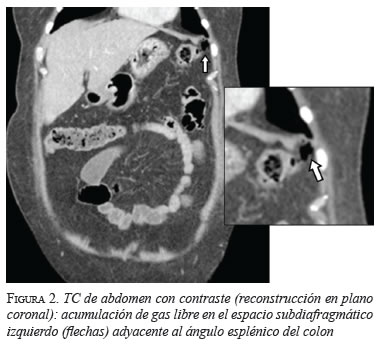

En las tres pacientes, la TC abdominal con contraste mostró el neumoperitoneo pericólico o localizado a menos de 5 cm del asa inflamada sin aire distante (figuras 2 y 3); dos presentaron divertículos en el ángulo esplénico, colon descendente y sigmoide, y una en el colon sigmoide únicamente.